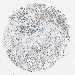

CANCER BREAST CANCER Show tissue menu

BRCA TCGA BRCA VALIDATION PROTEIN EXPRESSION

ANTIBODIES

AND

VALIDATION